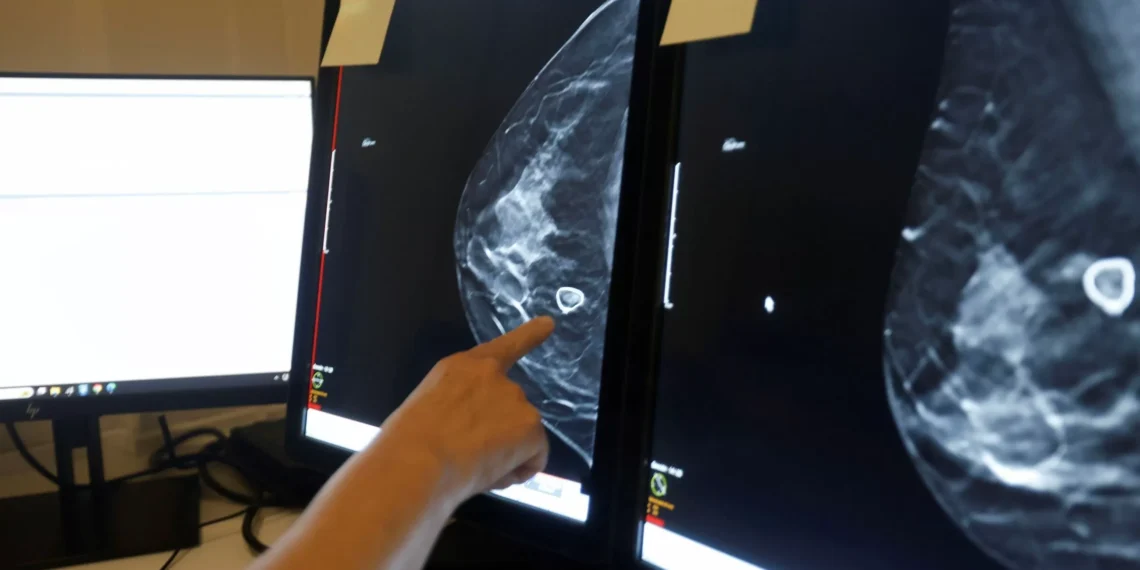

Una investigación reciente ha demostrado que la inmunización personalizada puede ser una herramienta efectiva en la lucha contra el cáncer. Un equipo de científicos ha llevado a cabo un estudio con 14 pacientes, en el que se ha demostrado que esta técnica puede entrenar a las células inmunitarias para atacar proteínas tumorales específicas.

En este estudio, los investigadores trabajaron con pacientes que padecían diferentes tipos de cáncer, como el de mama, pulmón y colon. A cada uno de ellos se les administró una vacuna personalizada, diseñada específicamente para entrenar a su sistema inmunológico para admitir y atacar las proteínas tumorales presentes en su cuerpo.

Los resultados fueron sorprendentes. En todos los pacientes, se observó una respuesta inmune específica contra las proteínas tumorales después de la vacunación. Además, en algunos casos, se observó una disminución en el tamaño de los tumores, lo que sugiere que la inmunización personalizada puede tener un efecto terapéutico en el cáncer.

Este estudio es un gran avance en la investigación del cáncer, ya que demuestra que la inmunización personalizada puede ser una herramienta efectiva para combatir esta enfermedad. Además, esta técnica tiene la ventaja de ser específica para cada paciente, lo que significa que se puede adaptar a las características individuales de cada caso.